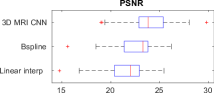

Image Quality Assessments: We compare HR ground-truth 3D volumes with upsampled LR raw data by measuring PSNR, SSIM and cross-correlation. We report SSIM, in particular, due to the well-understood metric properties that afford assessment of local structure correlation and reduced noise sensitivity. LR test imagery is upsampled in-plane () by factors of , to align with target ground-truth resolution. Quality metrics in Fig. 1 report improvements observed for an image upsampling factor of . This provides initial evidence in support of our hypothesis; learning problem and sensor specific deconvolutional filters to perform MRI stack upsampling is of benefit for subsequent resolution-sensitive tasks such as motion compensation and HR volume reconstruction.

By learning problem specific HR synthesis models, our 3D MRI CNN strategy outperforms the naïve baseline up-sampling, quantitatively improving the quality of the inferred HR imagery. Fig. 2 exhibits an example of qualitative improvement in orthogonal fetal MRI test-stack axes.